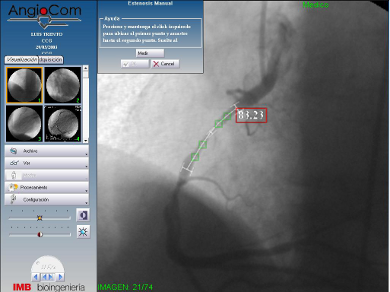

- Mediciones automáticas y manuales. Cardíacas, vasculares y cerebrales.